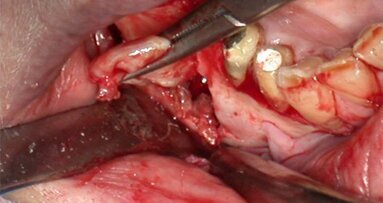

Case presentation: A 15-year-old male patient with a recurrent sinus tract involving the maxillary right incisors was referred for possible treatment with apical surgery. Root canal treatment and apical surgery had been undertaken unsuccessfully one year before. Radiographic examination revealed a radiolucent area surrounding the tooth apexes. A bone block was harvested from the apical area of the central incisor with ultrasound tips to gain access to the root end and apical surgery of both incisors was performed. The bone block graft was used to cover an apicomarginal bony defect of the maxillary lateral incisor. At the three-year follow-up, the teeth had no clinical signs or symptoms, and the periapical radiograph demonstrated complete healing around the apexes.

Conclusions: The use of a bone block graft to treat an apicomarginal defect in conjunction with apical surgery achieved complete healing of the periradicular tissue in this case.